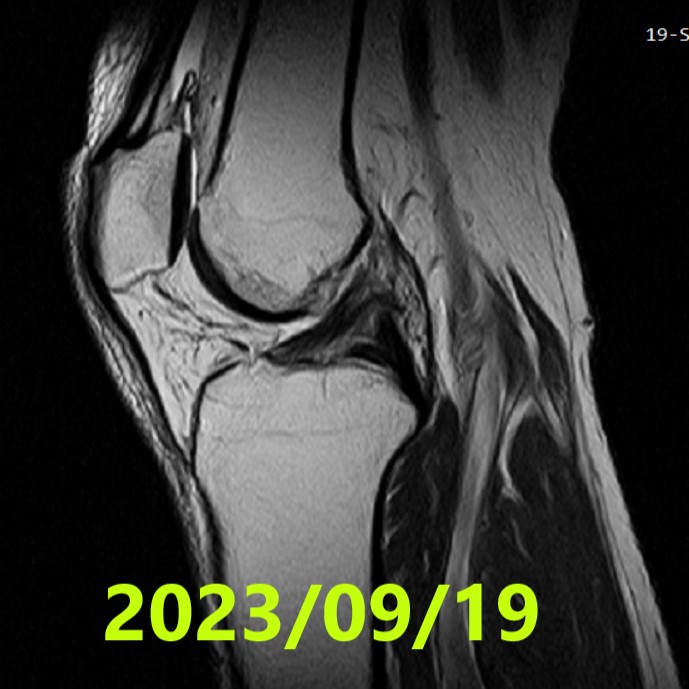

Final MRI Evaluation (~5 months)

- Date: 19 September 2023

- Assessment: ACLOAS Grade 0 (regeneration to normal structure) — Confirmed by consensus of 3 independent specialists

- Finding: The previously ruptured ligament achieved high-quality regeneration with morphology identical to a healthy ligament

- MRI #2 (2023/09/19): ACLOAS 0 — confirmed as high-quality regeneration to normal structure by 3 specialists